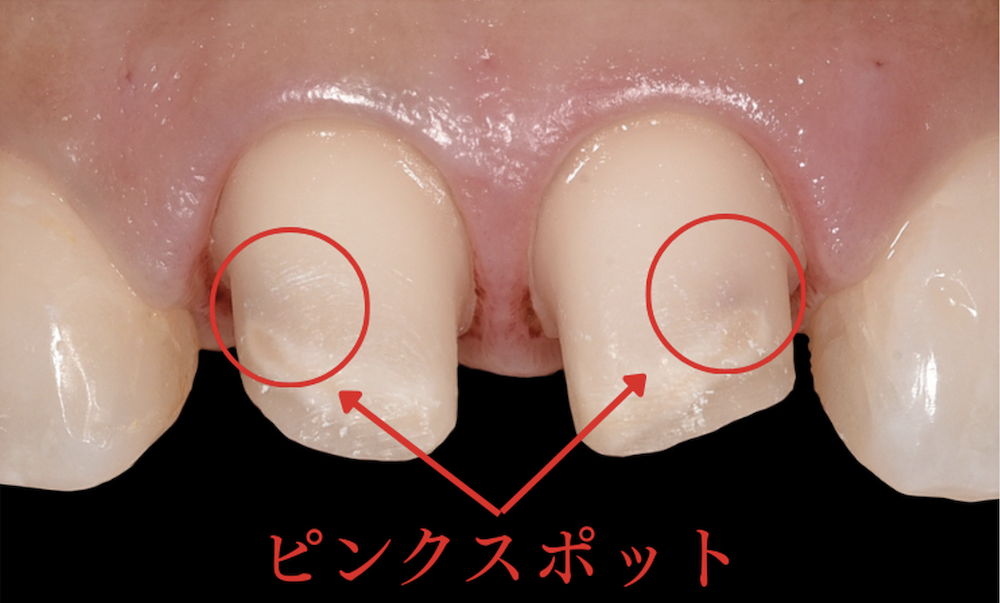

ピンクスポット

歯の内部には、歯の神経と共に血管があるため、歯を削って、神経近くになっていくと、内部の血管が見え始め、ピンク色や赤紫色のような色味になってきます。これをピンクスポットと言います。これ以上歯を削ると、神経がむき出しになり、神経を取らなければならなくなるため、神経を残すのであれば、これが削る限界となります。